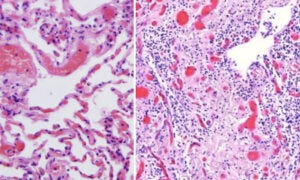

12. Lymphocytic infiltration and proliferative inflammation in lung tissue

On the left, we see healthy lung tissue, with air-filled spaces (the alveoli), delimited by delicate alveolar septa with embedded, blood-filled capillaries. We also see some larger blood vessels.

On the right hand side, we see lung tissue overrun by lymphocytes. The air-filled spaces have largely disappeared and been filled with scar (connective) tissue. This vaccine-injected patient would obviously have had very great trouble breathing.

Lymphocytic infiltration, inflammation and destruction were also observed in many other organs, including the brain, the liver, the spleen, and multiple glands. However, instead of illustrating them all, we will conclude the pathological evidence with another immunohistochemistry result, which strikingly shows the long duration of spike protein expression.